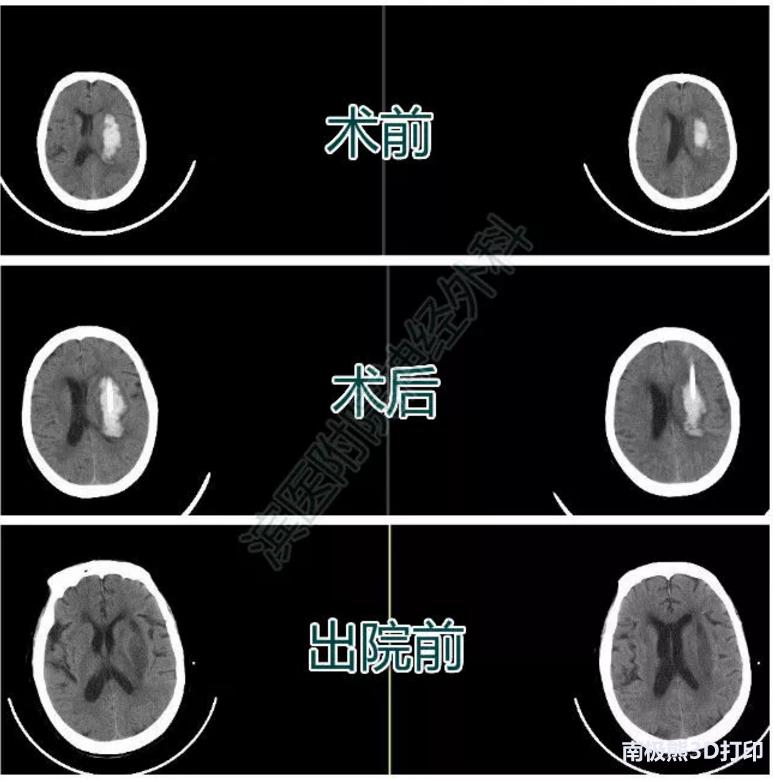

患者张某某,男,50岁,因“突发言语不清伴右侧肢体活动不利6小时”入院。

入院查体:嗜睡状态,呼喊睁眼,言语不清。双侧瞳孔直径约2mm,对光反应迟钝。右侧肢体肌力2级 ,左侧肢体5级。颅脑CT示左侧基底节区脑出血。入院后排除手术禁忌,行3D导板下经额部血肿腔穿刺术,术后复查颅脑CT如图,引流管位于血肿腔中心,穿刺位置满意。术后17天复查颅脑CT示血肿完全吸收,右下肢肌力4+,右上肢肌力4级。生活自理。

患者三影像资料

患者王某某,男,46岁,因“头痛伴左侧肢体活动不灵3天”入院。

入院查体:嗜睡状态,呼叫睁眼,言语尚可。双侧瞳孔直径约2mm,对光反应存在。左侧肢体肌力2级 ,右侧肢体肌力5级。颅脑CT示右侧基底节区脑出血。入院后排除手术禁忌,行3D导板下经额部血肿腔穿刺术,术后复查颅脑CT如图,引流管位于血肿腔中心,穿刺位置满意。辅以尿激酶血肿腔注入术后3天复查血肿已基本没有。

患者四影像资料